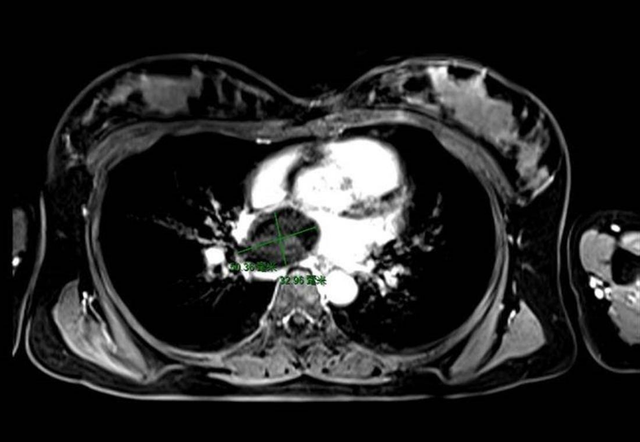

检查后结果吓了李大爷一跳,竟然是心脏里长了个“鸡蛋”大小的肉瘤,医生分析很可能就是心血管肉瘤,而肉瘤向周围组织浸润,影响心脏血流量,进而影响心脏正常功能,这种情况必须尽快手术!

心脏原发性肿瘤好发于左心房, 而心脏血管内皮肉瘤好发于右心房和右心室,由形成血管通道的恶性细胞组成。

在肉眼下,心脏血管肉瘤通常是深棕色或黑色出血性肿块,边界浸润。在显微镜下,心脏血管肉瘤浸润心肌,边缘不明显;血管通道不规则,多形性细胞常呈有丝分裂象。